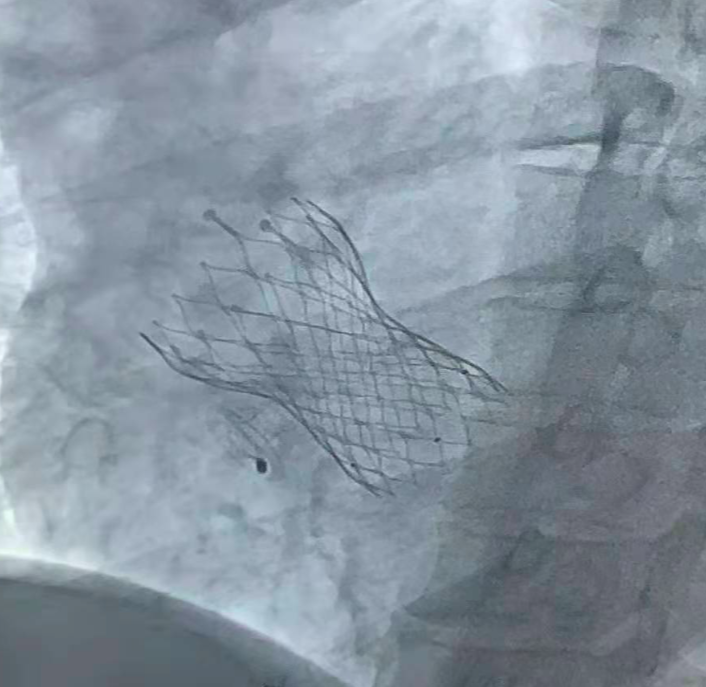

手术中局麻下使用经胸超声确认房间隔穿刺部位在卵圆窝附近,穿刺成功后在送入加硬导丝轨道支撑。根据患者病情及血流动力学结果,使用8mm球囊预扩张植入选择6mm心房分流器植入,透视下测量分流孔径5.8mm,孔径精准达标。植入后即刻效果显著,左房负荷超载和肺淤血明显减轻,血流动力学指标改善。肺动脉压降低至35/16(22)mmHg,左房压降低至24/9(14)mmHg,右房压9/1(4)mmHg,平均压力梯度维持在10mmHg,心指数2.3L/min*m2。体-肺分流量1.21。心房分流器植入部位准确,形态良好,血流动力学达到有效“3*3”目标值,效果理想,释放卸载分流器。

心房分流器植入后效果

患者术中即感到胸闷症状舒缓,术后活动耐量显著改善,六分钟步行距离升高至462米,纽约心功能II级,NT-proBNP 2160pg/ml。心脏超声测量分流孔径5.5mm,分流峰速2.2m/s,左心大小、功能、瓣膜反流较术前尚无明确变化。术后患者病情稳定,目前已顺利出院,期待后续随访结果。